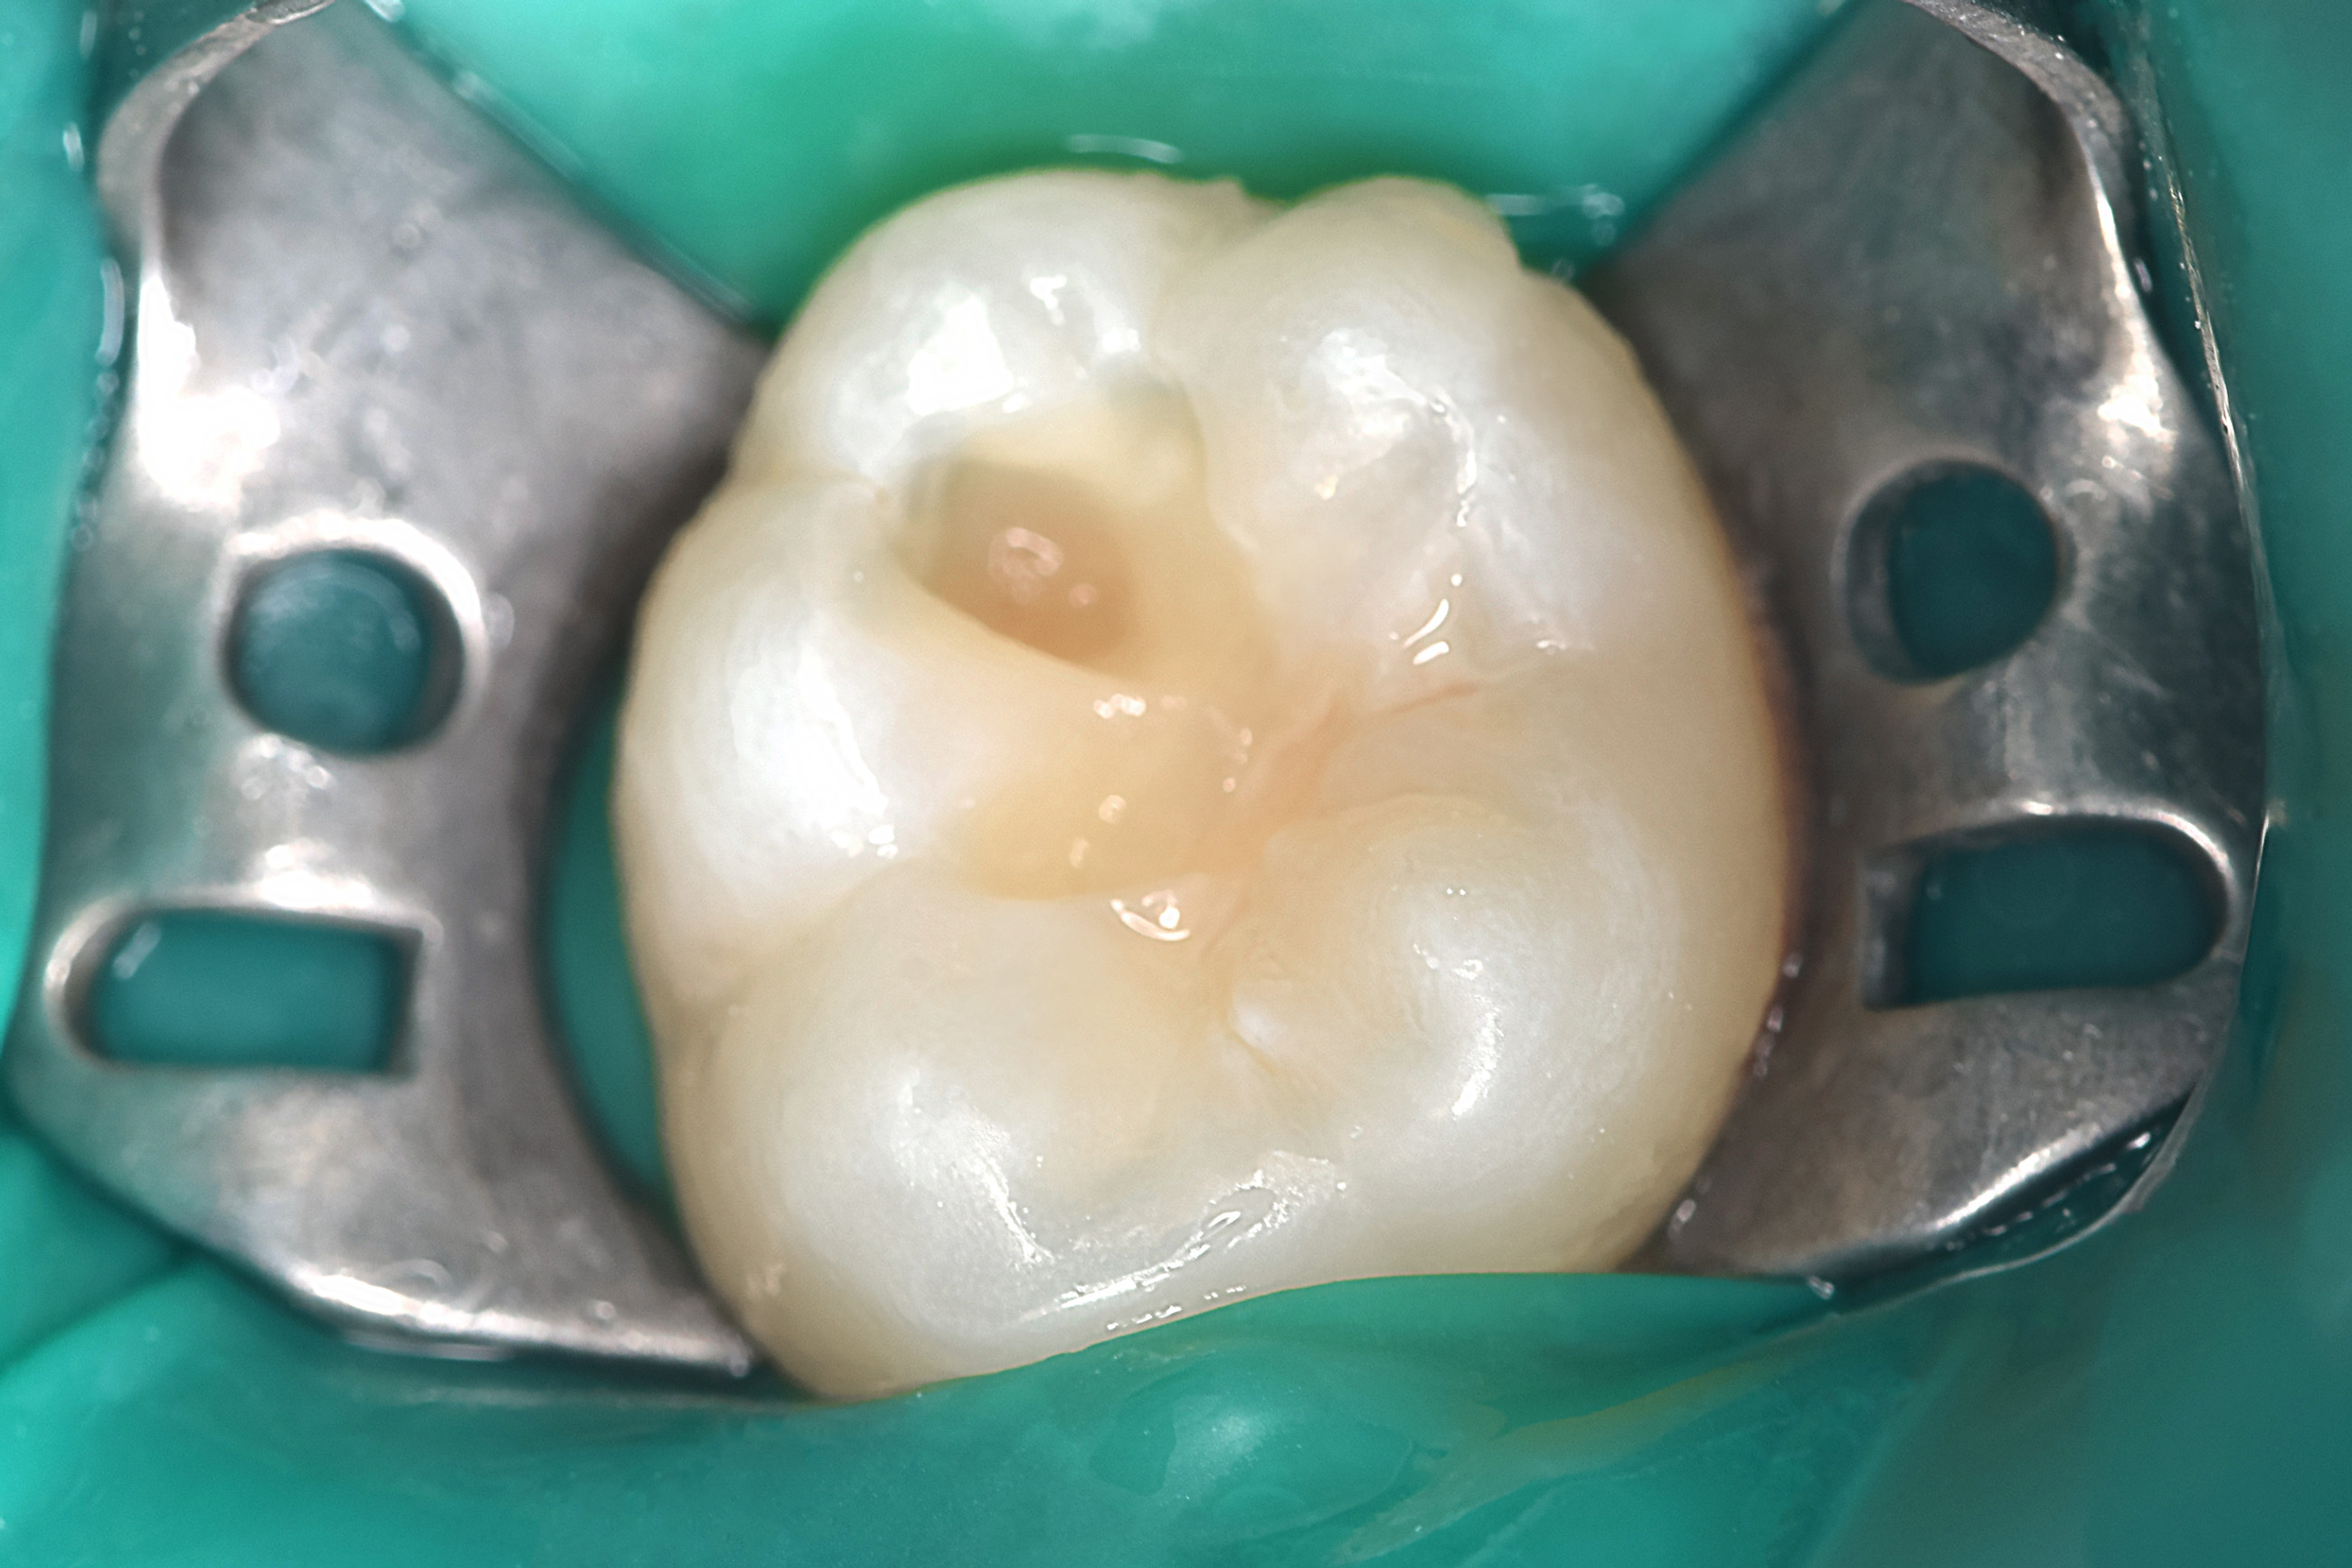

Ребенок 9 лет, пришел на прием с целью получения справки о здоровье полости рта. Был диагносцирован средний кариес постоянного зуба

Произведено лечение среднего кариеса, зуб восстановлен пломбировочным материалом